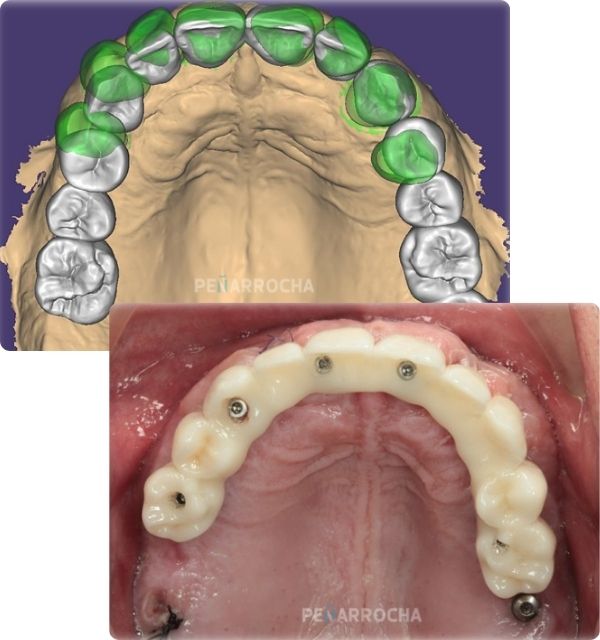

Realizamos un estudio completo mediante radiografías y tomografías 3D para determinar la calidad y cantidad de hueso disponible. Es importante evaluar si el paciente cumple con los requisitos necesarios para este tipo de implante.

En una única intervención quirúrgica, colocamos los implantes de titanio en el hueso maxilar o mandibular. Utilizamos técnicas de cirugía guiada para garantizar la máxima precisión.

funcionamiento tratamiento pasos 1 2 de los implantes de carga inmediata en valencia dres penarrocha cirugia e implantologia oral en valencia

3 - Prótesis fija provisional

Tras la colocación de los implantes, se fija una prótesis provisional que permite recuperar la funcionalidad y la estética de forma inmediata. Esta prótesis se adapta a los implantes y permite masticar alimentos blandos durante el período de cicatrización.

funcionamiento tratamiento pasos 3 4 implantes de carga inmediata en valencia dres penarrocha cirugia e implantologia oral en valencia